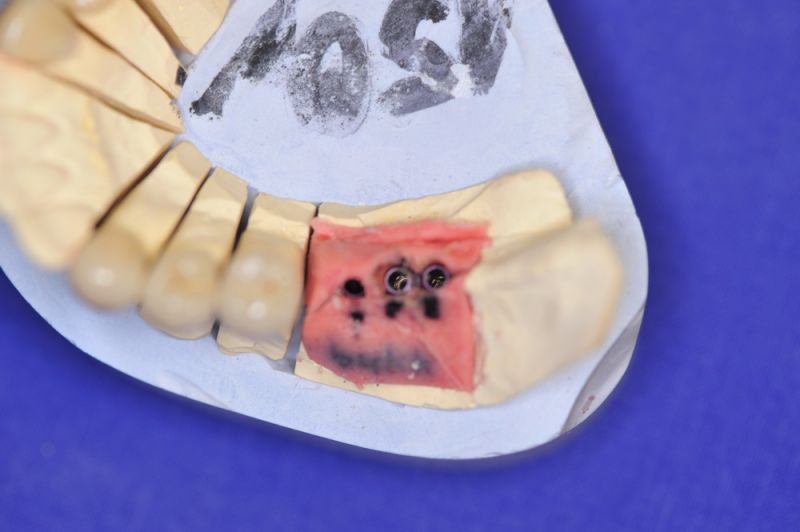

1. Notwendigkeit einer implantatgestützten Kronenversorgung mit der Vorgeschichte, dass die Patientin eine Vielzahl von Behandlern aufgesucht hatte, die eine Implantation im Unterkiefer als nicht durchführbar einschätzten.

2. Extrem schlechte knöcherne Verhältnisse im Unterkieferseitenzahnbereich, die sich intraoperativ noch einmal als ungünstiger darstellten, als bereits in den Voruntersuchungen erkennbar.

3. Sehr dünne Implantate, die von ursprünglich zwei je Kieferhälfte auf letztendlich drei je Kieferhälfte umgeplant werden mussten.

4. Notwendigkeit die Mundhygienefähigkeit der Arbeit auch unter sehr beengten Verhältnissen zu schaffen, um der Arbeit eine günstige Prognose mitzugeben.